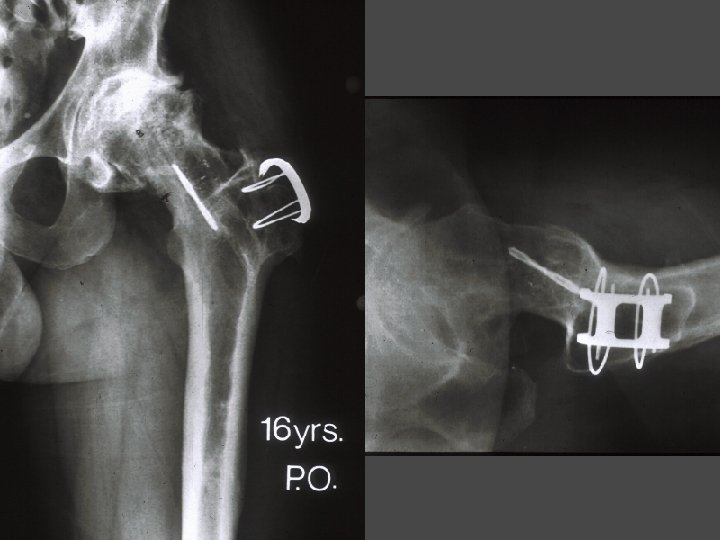

OSTEONECROSIS - ARTHROPLASTY Bipolar Yr No (yrs) F/U E/G Lachiewitz 88 31 (U/C)4. 6 48% 20% 7% Cabanela 90 23 (C) 9. 2 59% 12% 8% Cabanela 90 14 (U) 5. 3 57% 21% Learmonth 93 38 (C) 4. 7 Takaoka Hannsen 92 87 83 (U/C)5. 5 13 (U/C)5. 0 • Groin Thigh Revision Pain 43% 10. 5% 85% 23. 0% Cabanela ME: Bipolar vs. Total Hip Arthroplasty for Avascular Necrosis of the femoral head. CORR 261: 59 -62, 1990

6 yrs PR

OSTEONECROSIS - ARTHROPLASTY Bipolar • Abandoned • No advantages over THA • Main reason for failure is groin pain